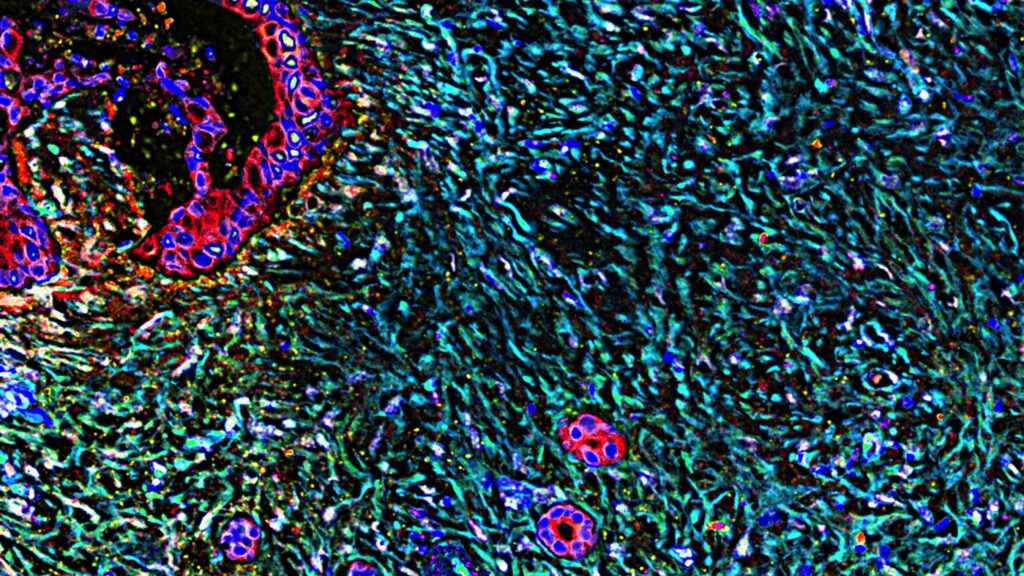

Image: STAT News